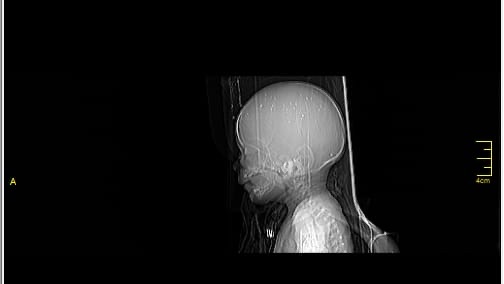

A 3-month-old baby in my family is facing a life-threatening brain condition. Medical reports and imaging confirm serious neurological injury that requires immediate, specialized treatment outside Gaza—care that is not available here.